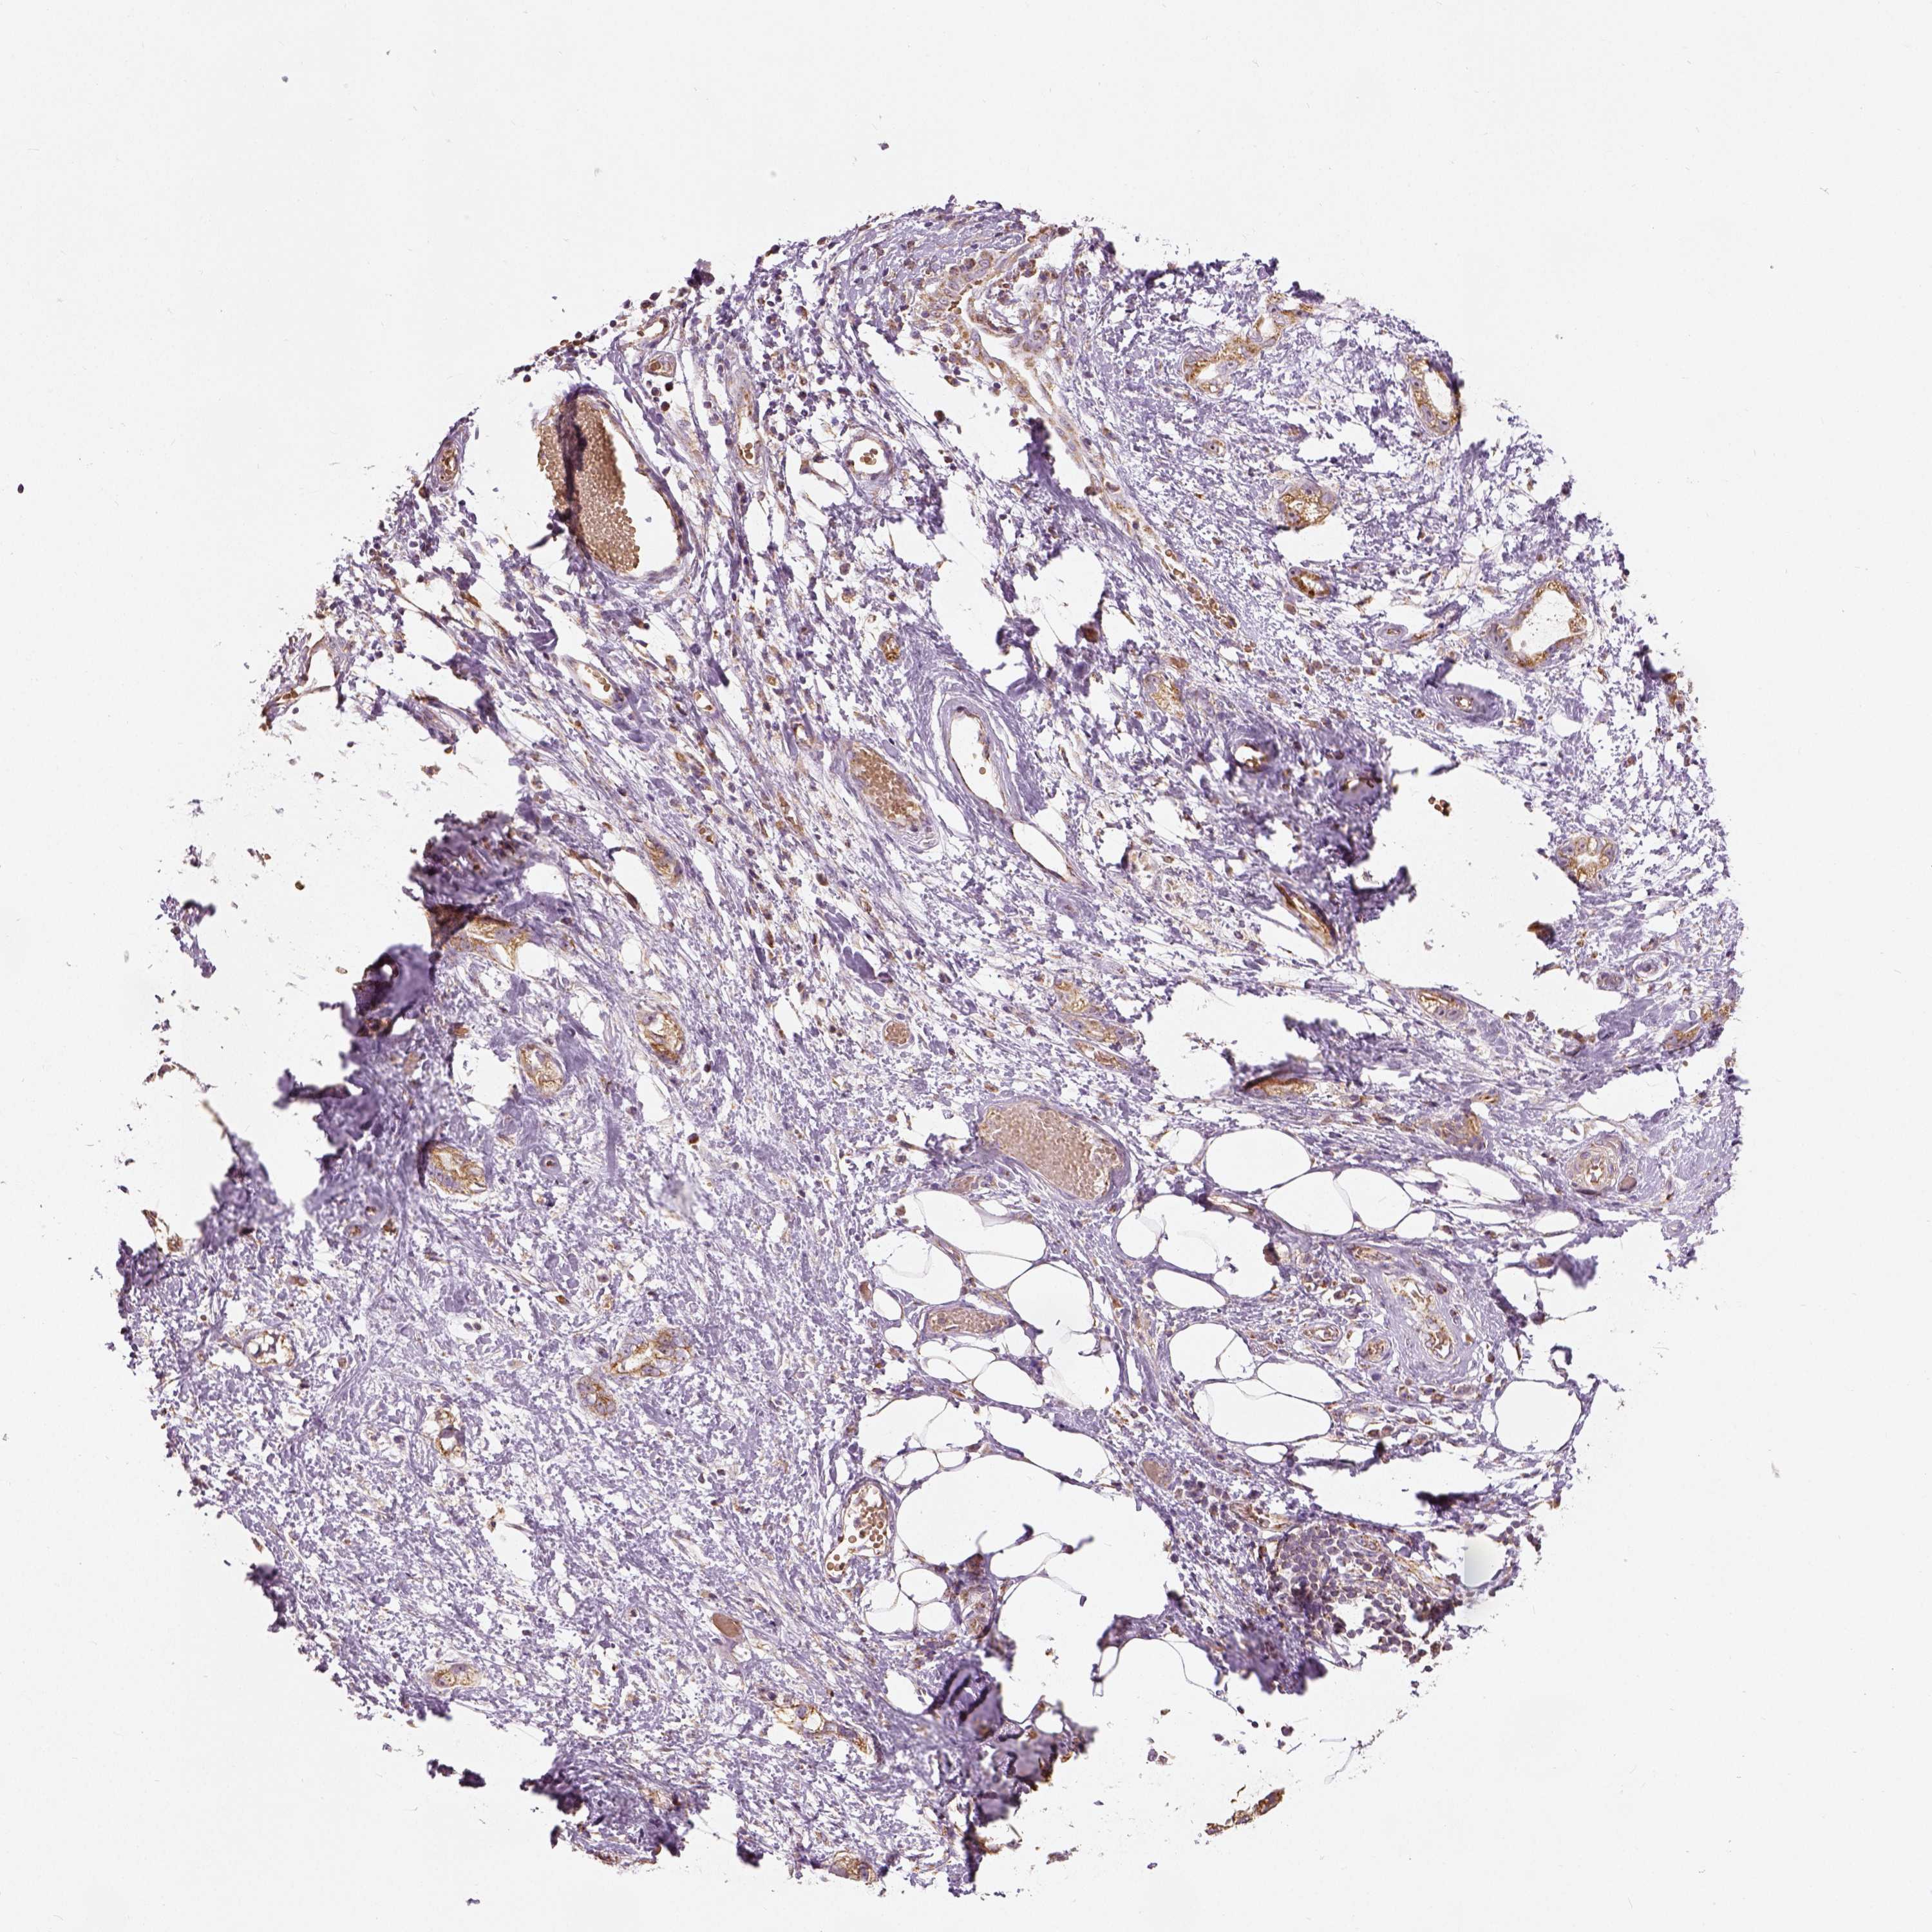

STOMACH CANCER - Protein expressioni

A mouse-over function shows sample information and annotation data. Click on an image to view it in a full screen mode. Samples can be filtered based on level of antibody staining by selecting one or several of the following categories: high, medium, low and not detected. The assay and annotation is described here.

Note that samples used for immunohistochemistry by the Human Protein Atlas do not correspond to samples in the TCGA dataset.

Antibody stainingi

Antibody staining in the annotated cell types in the current human tissue is reported as not detected, low, medium, or high, based on conventional immunohistochemistry profiling in selected tissues. This score is based on the combination of the staining intensity and fraction of stained cells.

Each image is clickable and will lead to virtual microscopy that enables deeper exploration of all samples and also displays staining intensity scores, fraction scores and subcellular localization as well as patient and tissue information for each sample.

Antibody HPA036978

Antibody HPA036979

Antibody CAB068215

Staining

High

Medium

Low

Not detected

Intensity

Strong

Moderate

Weak

Negative

Quantity

>75%

75%-25%

<25%

None

Location

Nuclear

Cytoplasmic/membranous

Cytoplasmic/membranous,nuclear

Adenocarcinoma, NOS